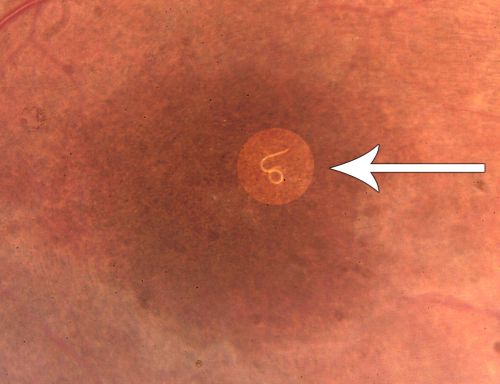

DUSN - Diffuse Unilateral Subacute Neuroretinitis - Nematode